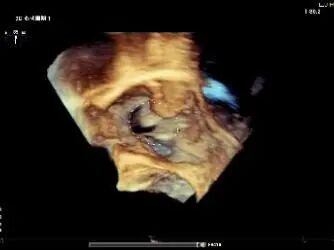

Tricuspid Valve Annuloplasty Stage:Subsequently, via the right internal jugular vein approach, the K-clip® transcatheter tricuspid valve annuloplasty system was delivered to the right atrium. With the assistance of three-dimensional ultrasound stereoscopic views, a 12T clip was successfully implanted at the posteroseptal commissural annulus of the tricuspid valve, and a 14T clip at the anteroposterior commissural annulus, achieving effective constriction of the dilated annulus. Immediate postoperative assessment demonstrated that tricuspid regurgitation was improved from severe (4+) to mild (1+) instantaneously.

Annuloplasty Effect: The tricuspid valve annulus area was reduced from 9.96 cm² to 4.6 cm², representing a 53% decrease in annulus area.

Postoperative regurgitation (trivial)

Surgical Outcome: Severe tricuspid regurgitation (4+) was reduced to mild tricuspid regurgitation (1+).